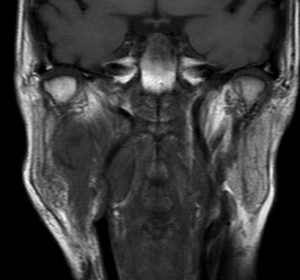

右はがドリニウム増強MRIです。NF-1患者さんの右深頸部のplexiform neurofibromaに発生したものです。通常の神経鞘腫に比較して境界が不鮮明で増大速度が早いことが特徴です。

- MRIでは境界不鮮明な不規則に増強される腫瘍です